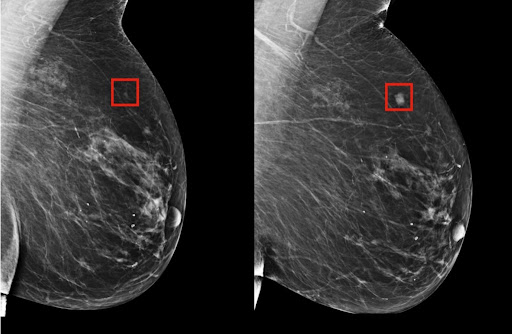

Predecir un cáncer de mama cinco años antes de que aparezca, posible gracias a la inteligencia artificial

A pesar de los notables avances que ha habido en los últimos años en materia de tecnología de diagnóstico, así como del aumento de campañas dirigidas a promover la autoexploración, muchas pacientes de cáncer de mama siguen recibiendo el diagnóstico en estadios avanzados de la enfermedad . Esto se traduce (en el mejor de los casos) en pasar por tratamientos agresivos con la ansiedad de un resultado incierto. De ahí que, desde hace un tiempo, identificar a las pacientes en riesgo antes de que aparezca la enfermedad sea la meta a la que se dirigen muchas investigaciones vinculadas al cáncer de mama. Por eso es tan importante el logro que acaban de cosechar los investigadores del Hospital General de Massachusetts y el CSAIL (el Laboratorio de Informática e Inteligencia Artificial del MIT): la creación de un modelo de deep learning capaz de predecir a partir de una mamografía si la paciente es propensa a desarrollar un cáncer de mama en el futuro , concretamente a 5 años vista. En...